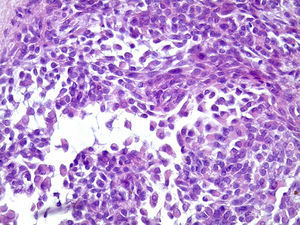

Os cortes histológicos, corados em hematoxilina e eosina, mostraram neoplasia de glândula salivar benigna, constituída por células epiteliais e mioepiteliais, parcialmente envolvida por fina cápsula de tecido conjuntivo fibroso (fig. 5). As células epiteliais encontravam‐se formando lençóis ou estruturas ductiformes, enquanto as células mioepiteliais formavam áreas mixoides, hialinas (fig. 6) ou exibiam aspecto plasmocitoide (fig. 7). O diagnóstico de adenoma pleomórfico foi confirmado. Paciente queixou‐se de desconforto no palato quando se alimentava, durante as 2 primeiras semanas após cirurgia. O paciente está sendo acompanhado clinicamente e, 2 anos após a cirurgia, não apresenta sinais de recidiva da lesão (fig. 8).

Os cortes histológicos mostraram neoplasia benigna de glândula salivar, envolvida por cápsula de tecido conjuntivo fibroso (fig. 14). O parênquima neoplásico é constituído por células epiteliais dispostas em lençóis e estruturas ductiformes, além de células mioepiteliais formando áreas mixoides e hialinas (fig. 15) ou apresentando‐se com morfologia plasmocitoide (fig. 16). O diagnóstico de adenoma pleomórfico foi confirmado. A paciente relatou ausência de dor no pós‐operatório e manteve utilização da placa de acrílico por 4 semanas. A paciente encontra‐se em acompanhamento e o exame clínico após 2 anos da remoção cirúrgica mostrou adequada cicatrização e ausência de sinais de recidiva da lesão (fig. 17).